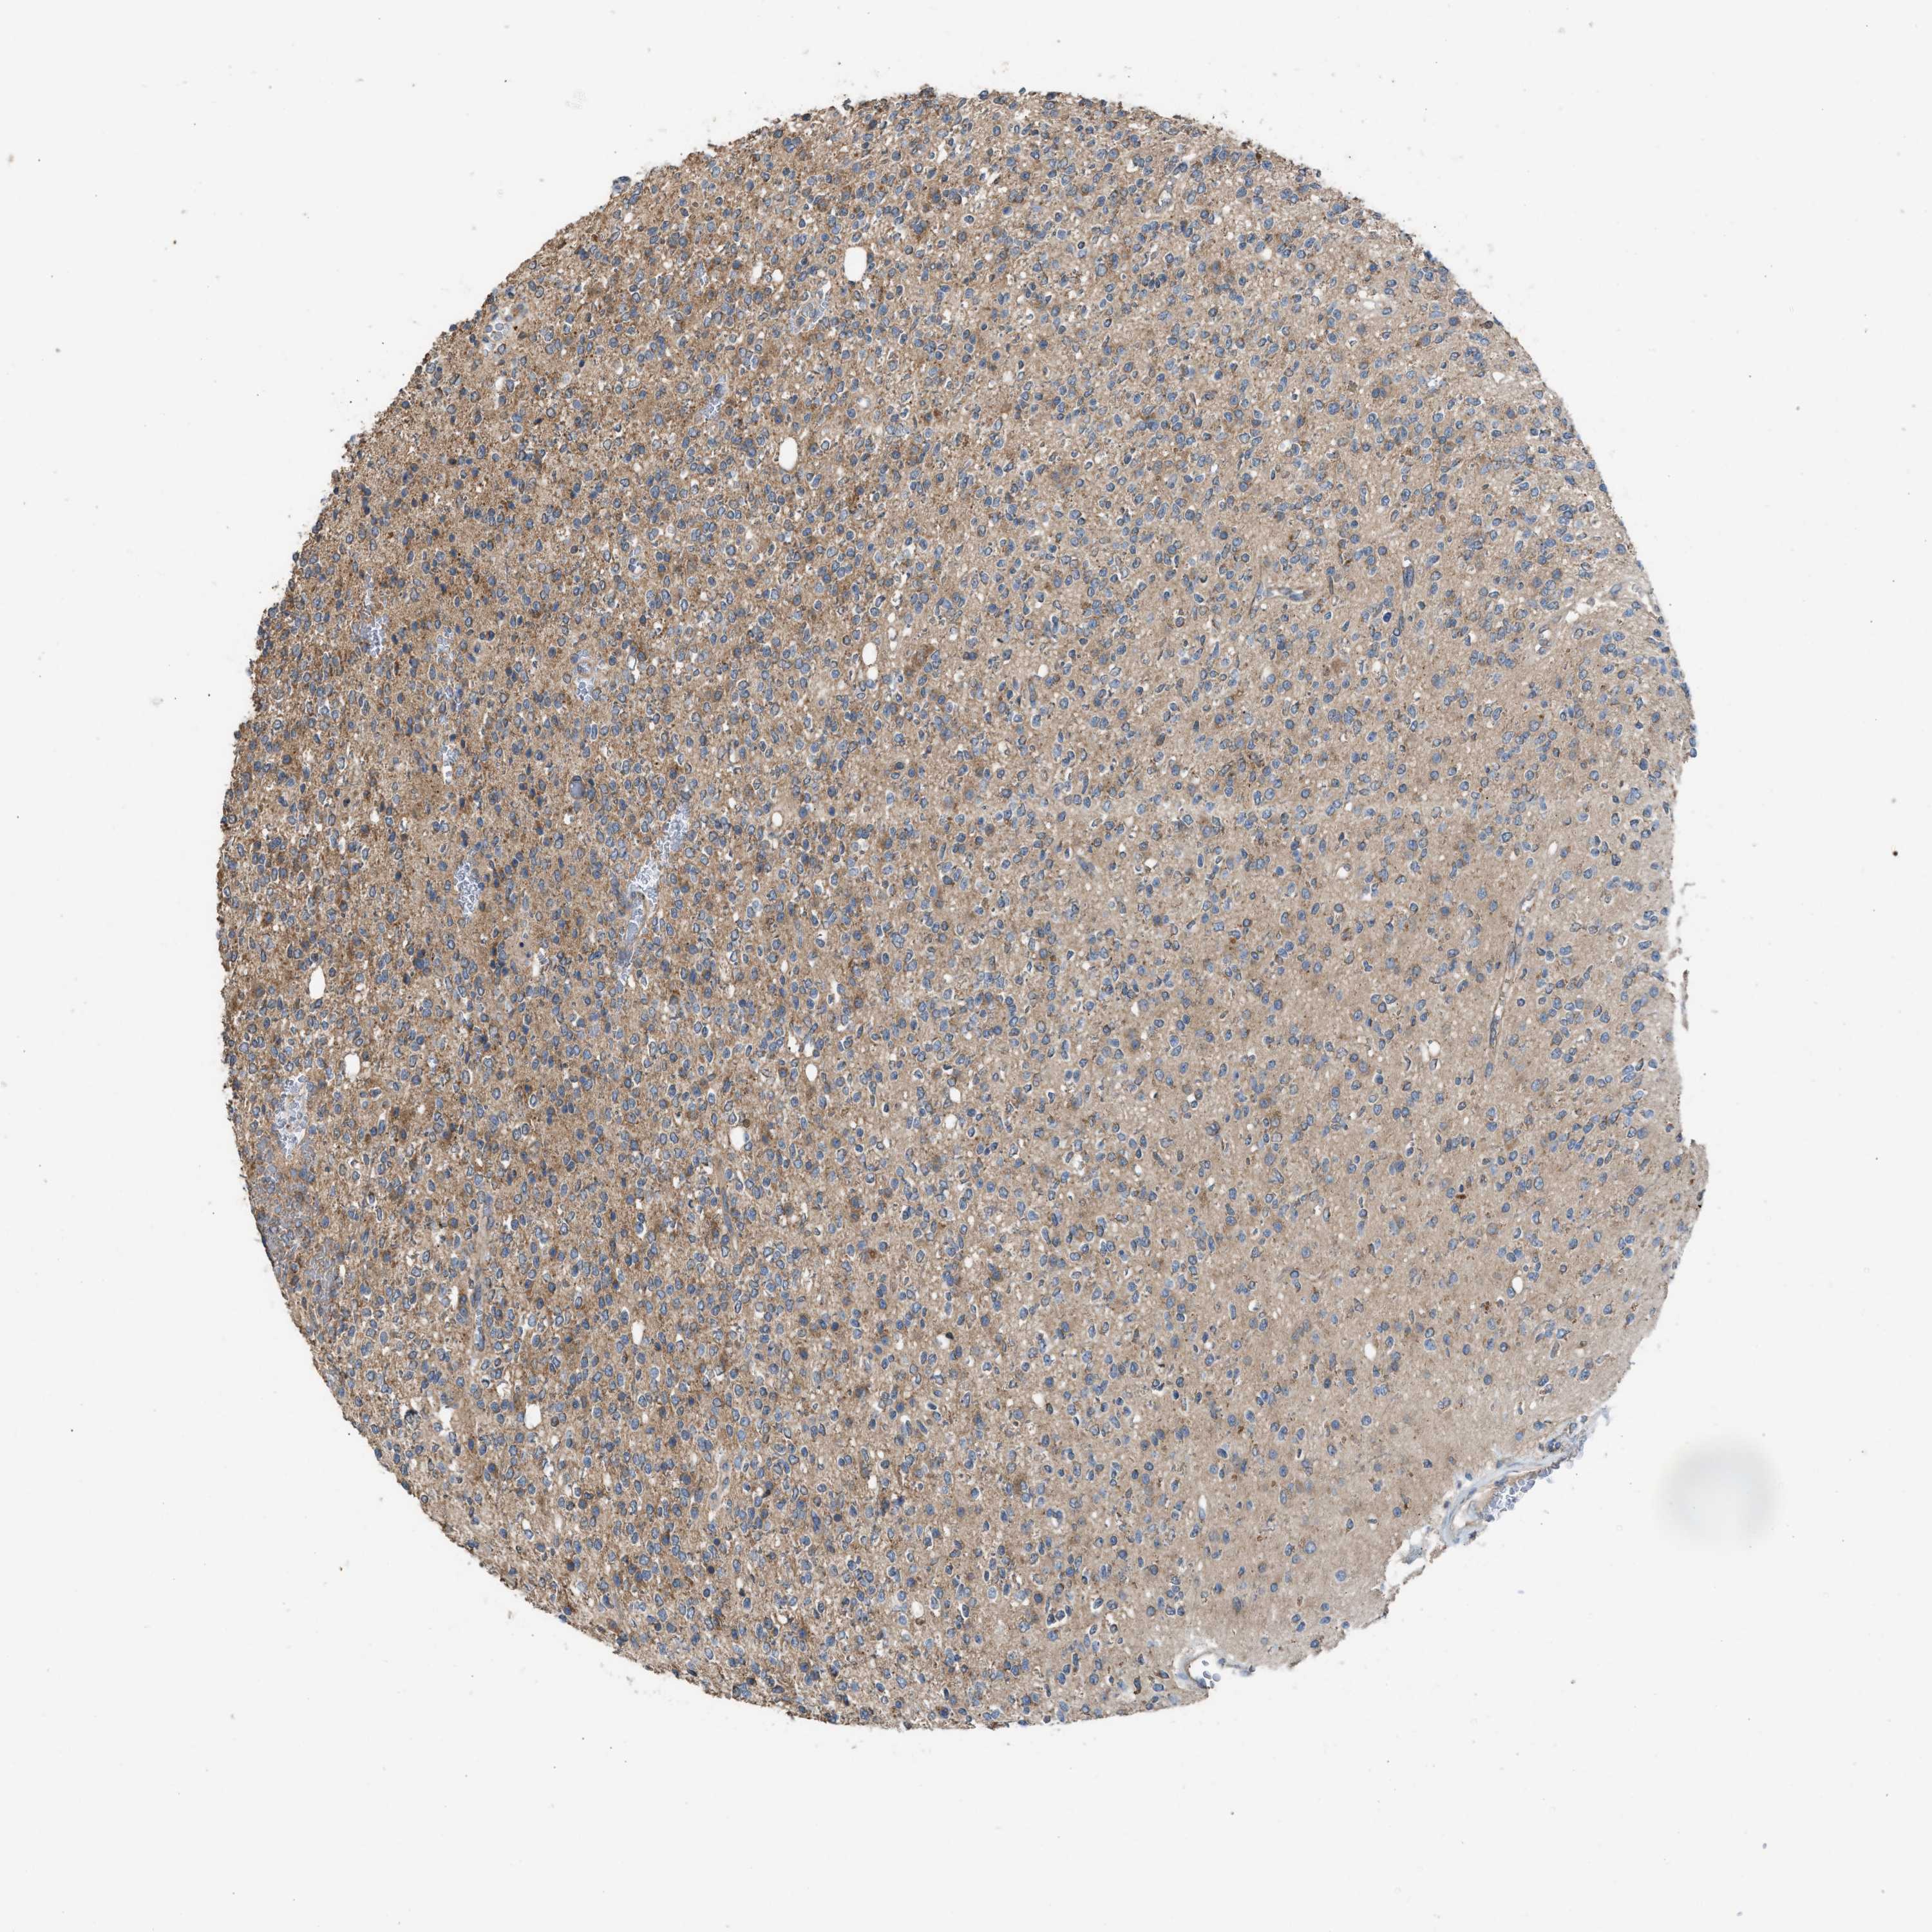

GLIOMA - Protein expressioni

A mouse-over function shows sample information and annotation data. Click on an image to view it in a full screen mode. Samples can be filtered based on level of antibody staining by selecting one or several of the following categories: high, medium, low and not detected. The assay and annotation is described here.

Note that samples used for immunohistochemistry by the Human Protein Atlas do not correspond to samples in the TCGA dataset.

Antibody stainingi

Antibody staining in the annotated cell types in the current human tissue is reported as not detected, low, medium, or high, based on conventional immunohistochemistry profiling in selected tissues. This score is based on the combination of the staining intensity and fraction of stained cells.

Each image is clickable and will lead to virtual microscopy that enables deeper exploration of all samples and also displays staining intensity scores, fraction scores and subcellular localization as well as patient and tissue information for each sample.

Antibody HPA021545

Antibody HPA021849

Staining

High

Medium

Low

Not detected

Intensity

Strong

Moderate

Weak

Negative

Quantity

>75%

75%-25%

<25%

None

Location

Nuclear

Cytoplasmic/membranous

Cytoplasmic/membranous,nuclear

Glioma, malignant, High grade

Glioma, malignant, Low grade